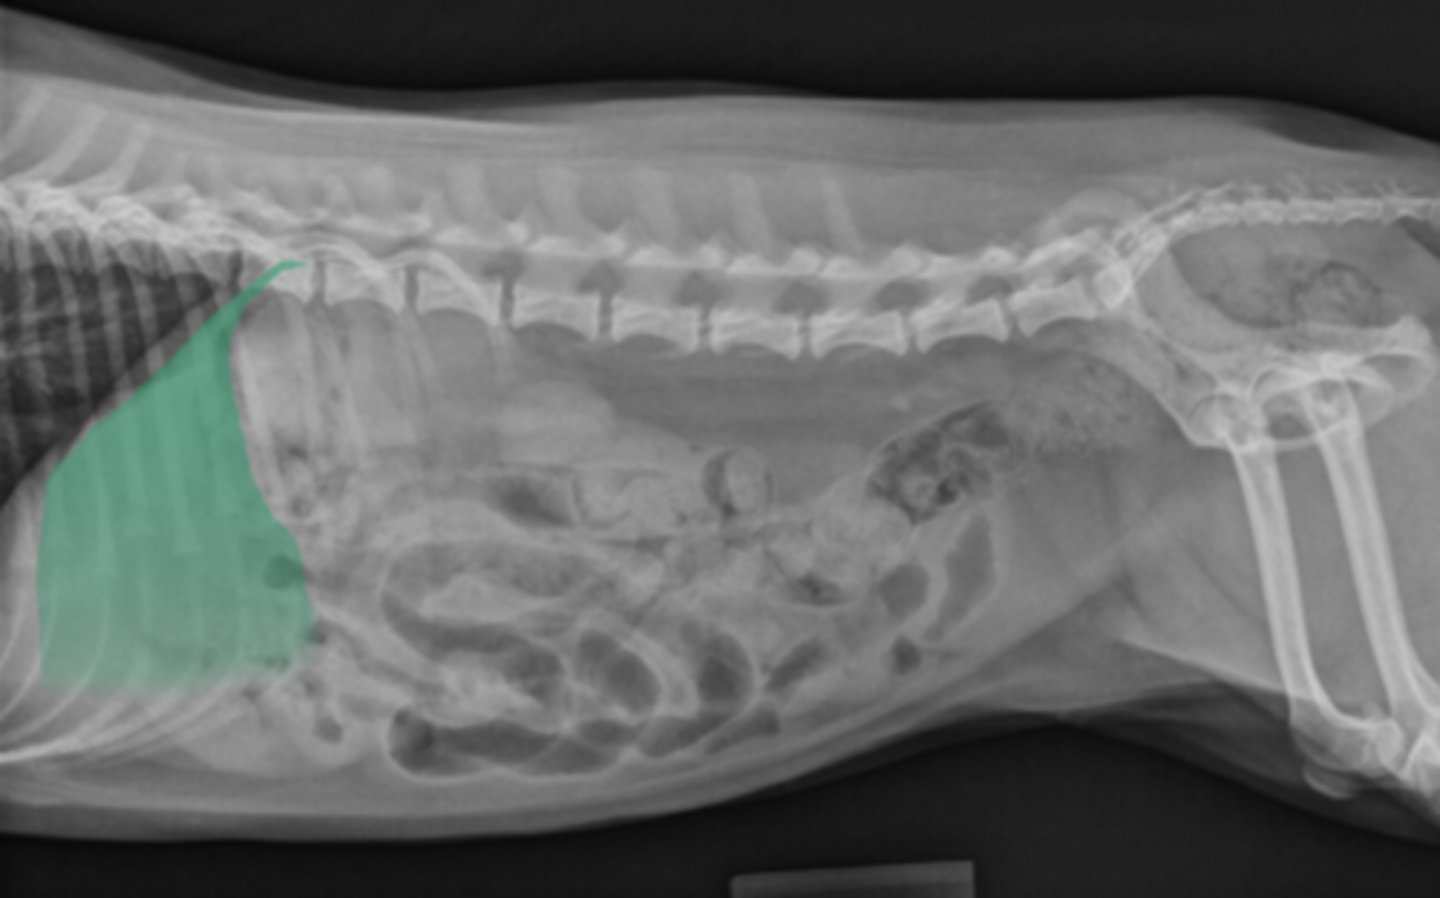

Renomegaly

Cat image with large kidneys and ureters- what is this called?

left kidney

What structure is this?

What organ is this?